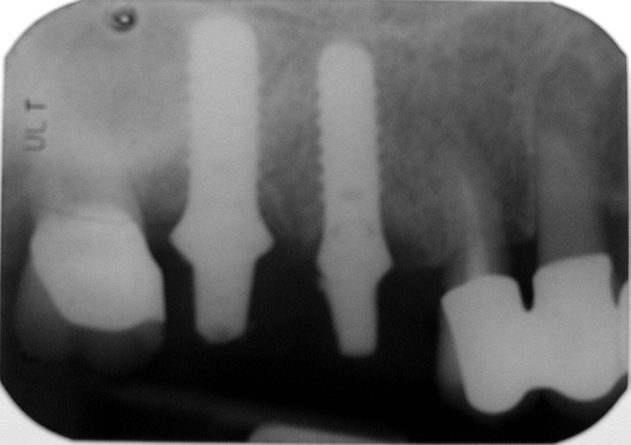

Při ztrátě molárů a premolárů v horní čelisti a jejich náhradě implantáty se často setkáváme s nedostatečnou vertikální nabídkou kosti pod čelistní dutinou, často doprovázenou i nedostatečnou horizontální nabídkou a sníženou kvalitou kosti

(v oblasti 2. premoláru v 50%, v oblasti moláru až v 80% případů nedostatečná kostní nabídka)

Od roku 1985 je tento problém řešen augmentační operací nazývanou sinus lift.

Jedná se o vyzvednutí membrány, která čelistní dutinu vystýlá, pod vyzvednutou membránou vznikne kapsa, kam se umístí augmentační materiál, do kterého se zavedou implantáty.

- Uzavřený, interní, vnitřní, crestální sinus lift

- Otevřený, externí, vnější, laterální sinus lift